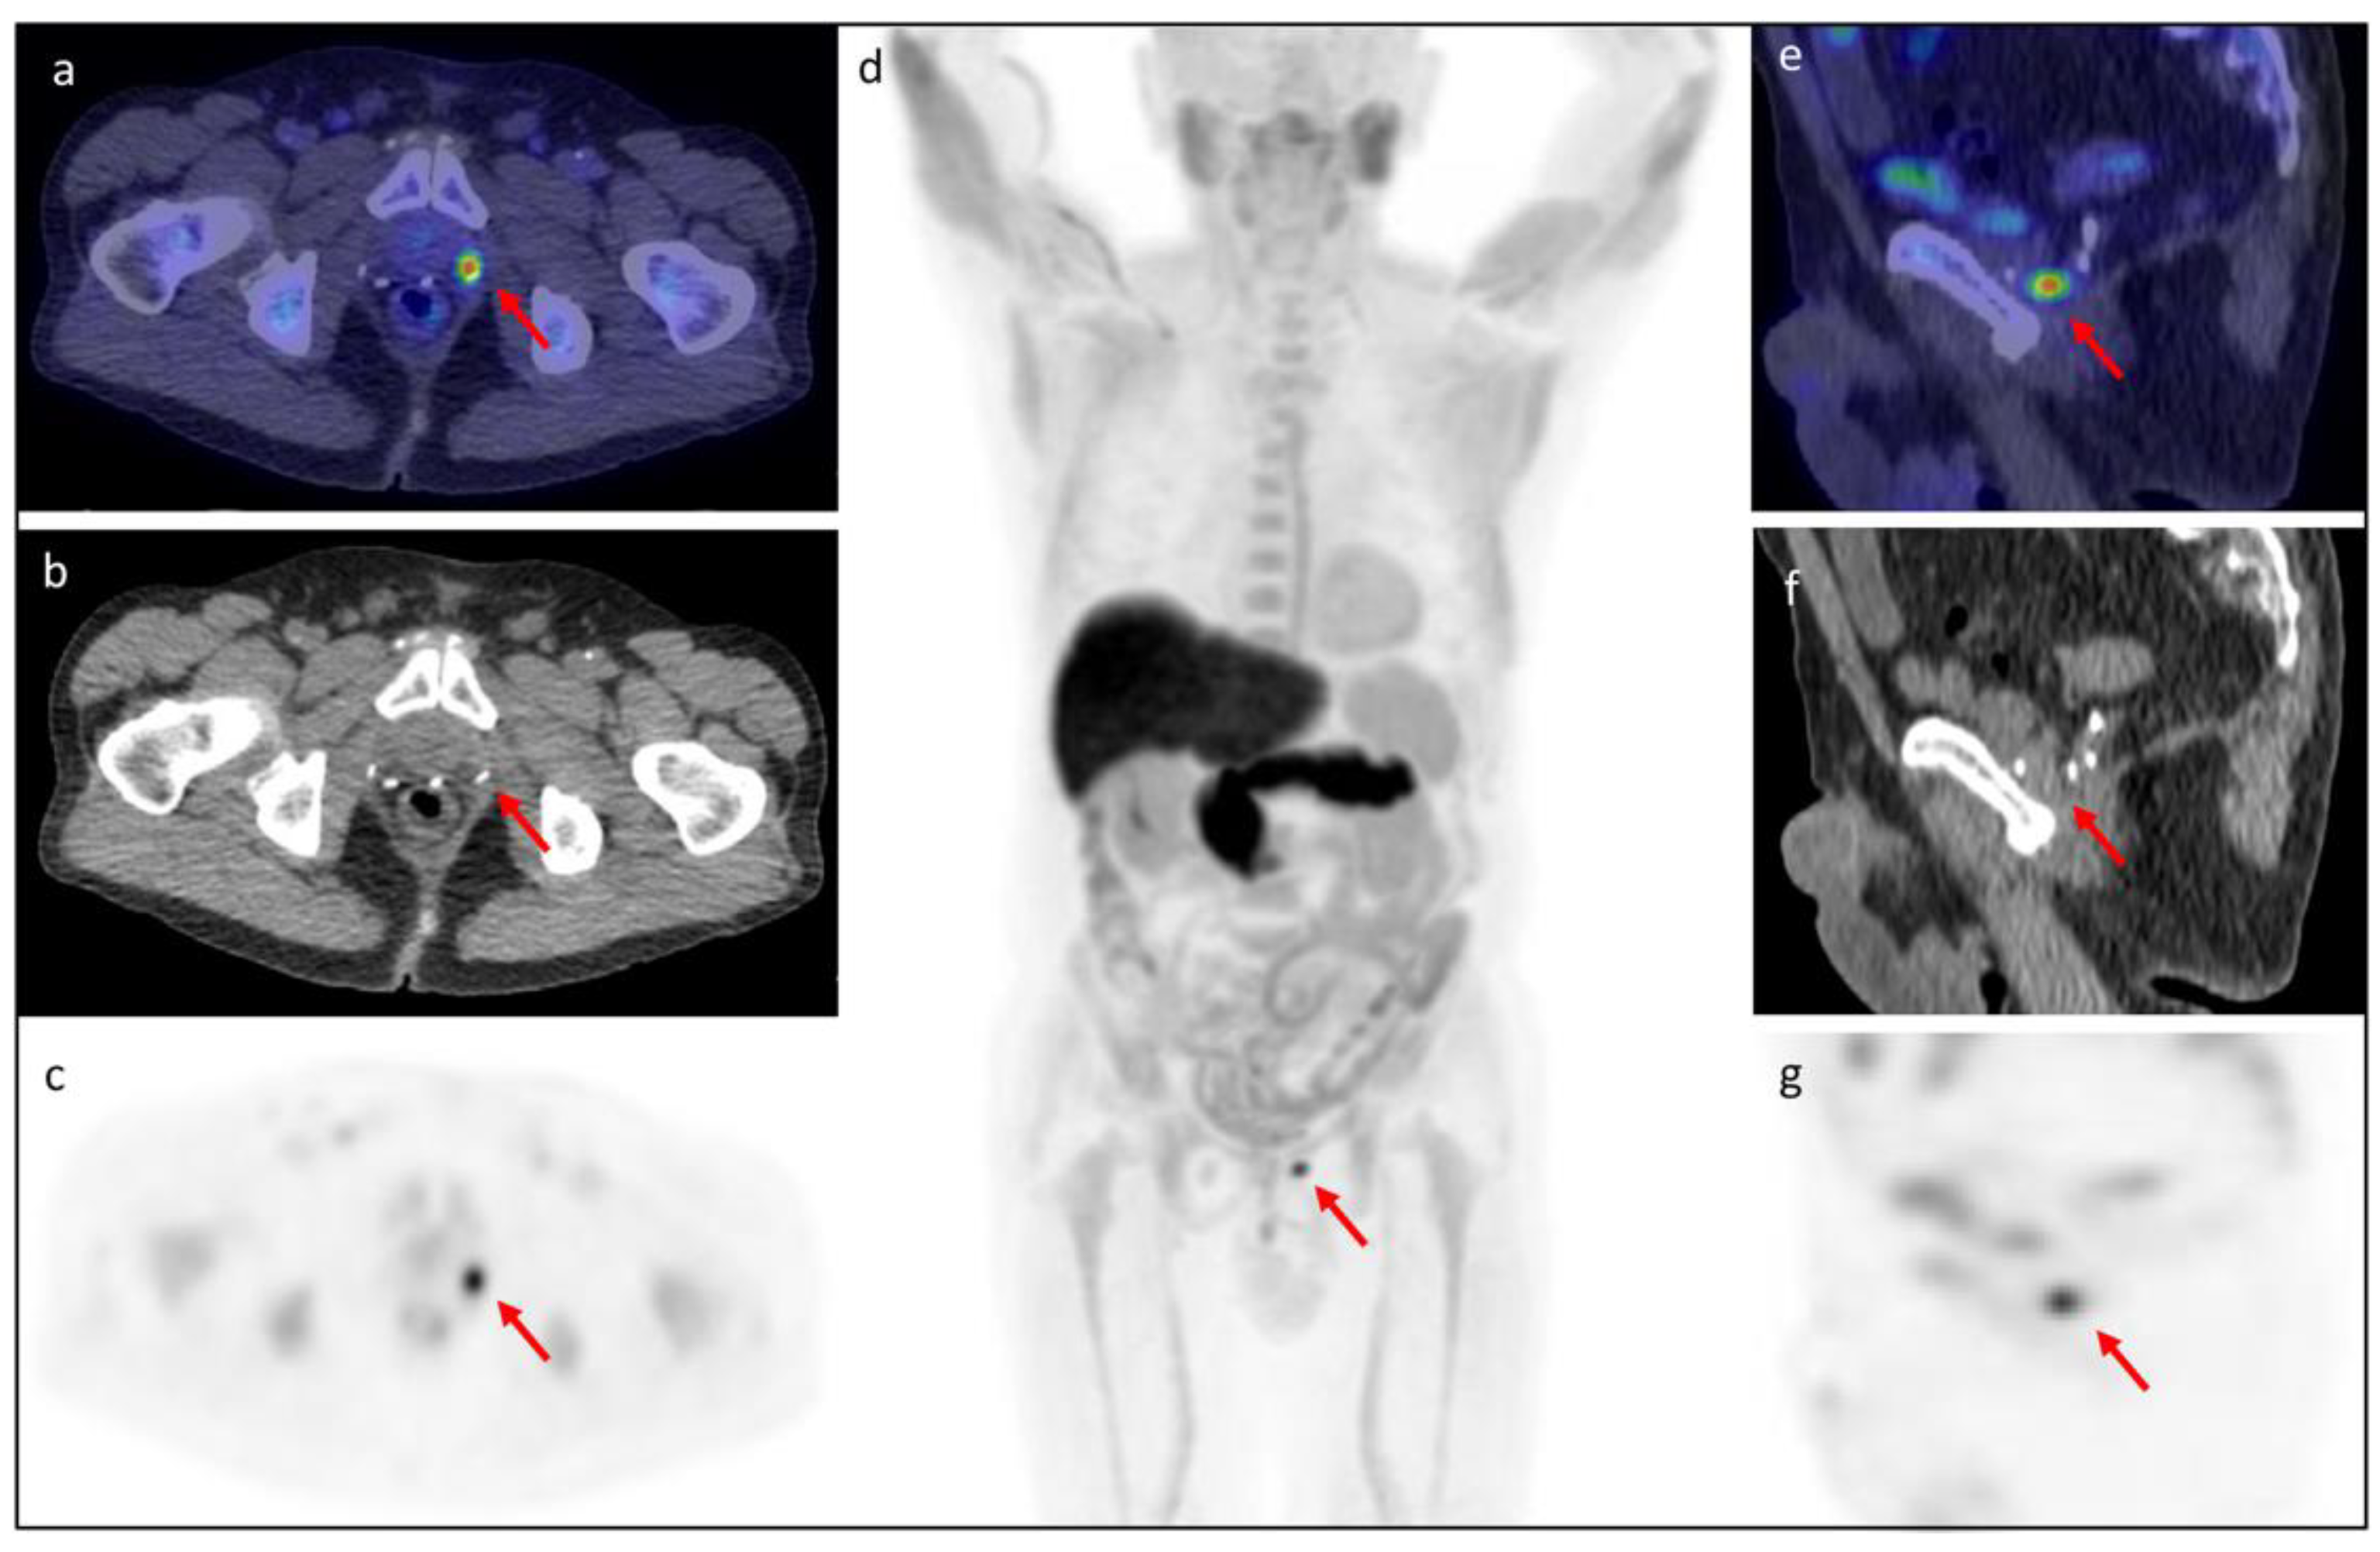

3.5. Clinical Cases